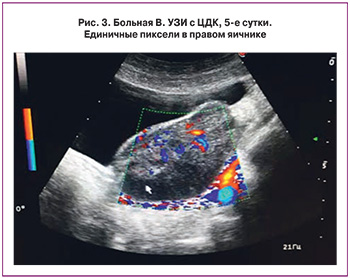

Выполнена деторсия, во время которой произошло повреждение отечного яичника, выделилось около 1 мл темной крови. Сомнения в нежизнеспособности придатков матки имелись, однако решено было провести органосохраняющую операцию, так как перед операцией у ребенка отмечался выраженный болевой синдром, что давало надежду на сохранность яичника. В послеоперационном периоде при ЦДК зарегистрирован кровоток лишь на 5-е сутки (рис. 3).

Спустя 1 месяц после операции размеры яичника соответствовали контралатеральному, кровоток не снижен, в нем определяются фолликулы.